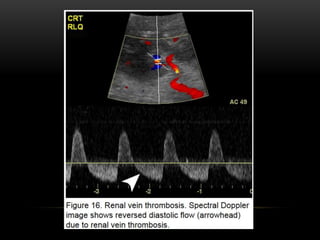

Venous thrombosis results in a high-resistance vascular circuit and can

result in subsequent reversal of diastolic flow in the arterial waveform;

however, reversed diastolic flow is a nonspecific finding which can be

seen in severe rejection, severe pyelonephritis, drug toxicity and extrinsic

compression.